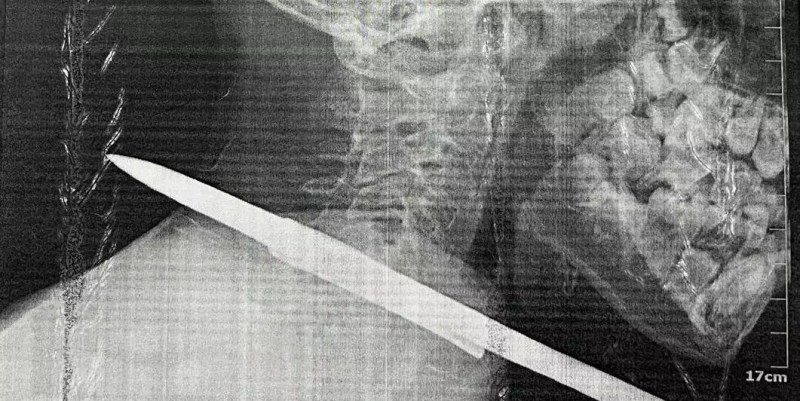

Um arpão de pescador foi retirado do pescoço de uma criança de 11 anos após cirurgia no Hospital Municipal de Santarém Dr. Alberto Tolentino Sotelo, na última segunda-feira (07/10), no município de Santarém, na região oeste do Pará. O menino chegou no hospital depois de um acidente grave durante uma pescaria e passou por uma cirurgia de emergência para a retirada do objeto.

“No pescoço passam várias estruturas que são muito nobres para o nosso organismo. Passa ali a artéria carótida, a veia jugular, e o arpão estava atravessado a centímetros dessas duas estruturas. Então, por pouco, não foi um acidente muito grave. Foi um milagre”, relatou o médico cirurgião Augusto Aguiar, que fez a retirada de uma vara de arpão que estava atravessada no pescoço do paciente.

O cirurgião Augusto Aguiar, responsável pelo procedimento, analisou que a situação era potencialmente grave dada a localização. A cirurgia foi realizada sem complicações. “A cirurgia foi relativamente simples porque essas estruturas vitais foram poupadas, mas poderia ter sido um desastre. Podemos dizer que um milagre aconteceu ali, porque poderia ter sido uma situação extremamente grave e com potencial risco de vida. Foi um milagre”, enfatizou.